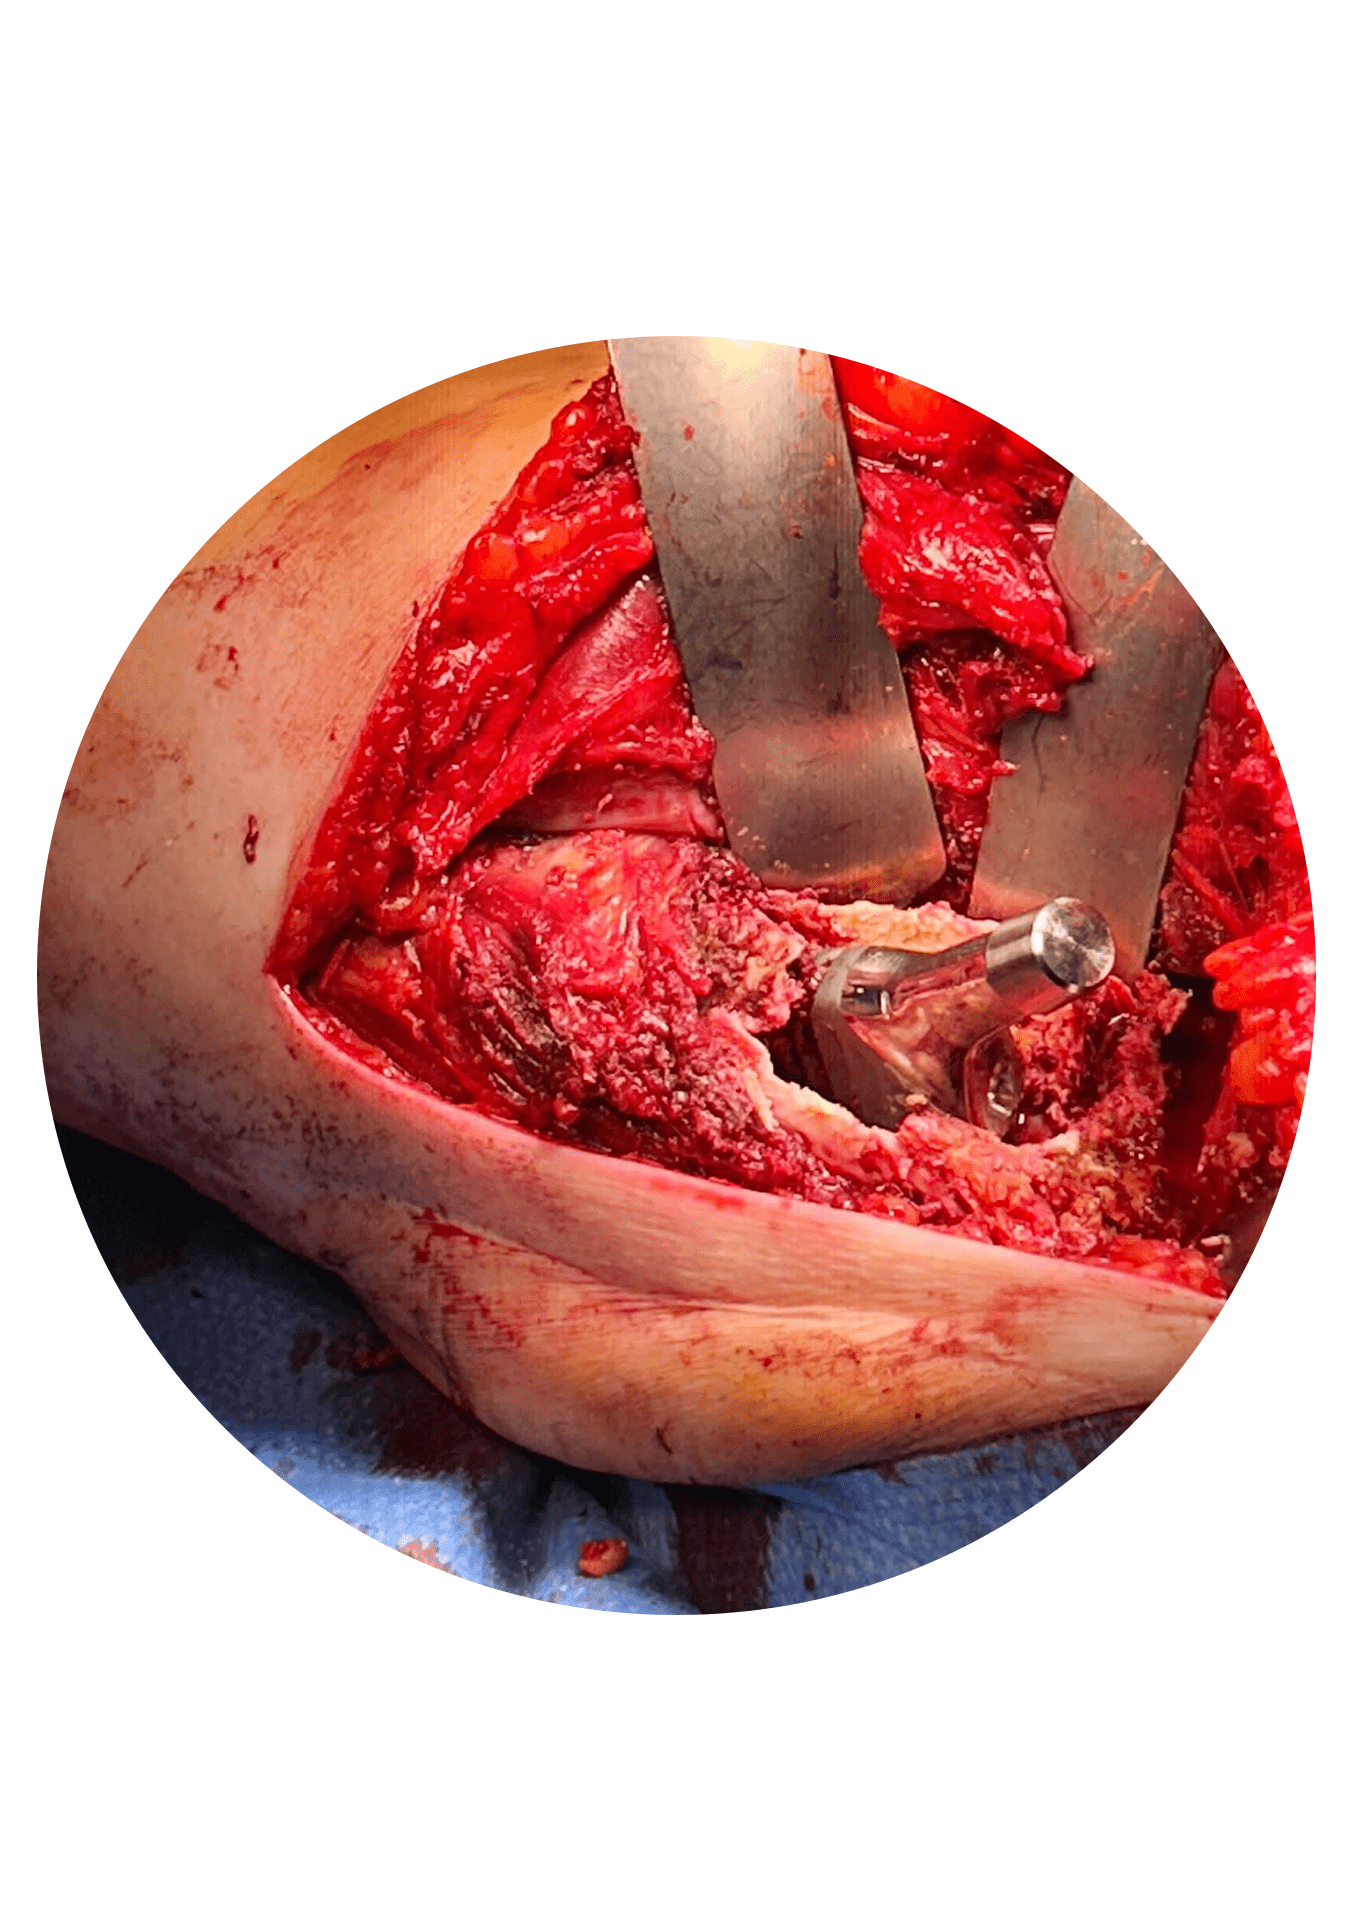

Primeiro: remoção do implante(s) deficiente(s) e preservação dos implantes competentes. Este é muitas vezes o momento mais complexo da cirurgia de revisão. O seu objetivo principal é remover apenas os implantes que precisam de ser substituídos e neste processo causar a menor lesão possível na estrutura óssea da articulação para facilitar a fase seguinte.

Em relação à abordagem cirúrgica esta deve ser adequada a cada caso e planeada em função do objetivo… que implantes remover? Que reconstruções são necessárias… Acetabulares? Femorais? Ambas? A via de abordagem por excelência para a cirurgia de revisão é a via posterior (corte na face posterior da anca na zona do glúteo com cerca de 15 a 20 cm… esta pode ser estendida consoante o objetivo da cirurgia). Em casos selecionados é possível usar a via usada na primeira cirurgia ou usar uma via diferente para facilitar a revisão.